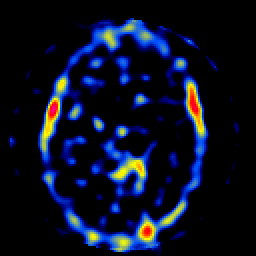

SPECT TL Study #8 -- Slice #28

[Home][Help][Clinical][Tour 1][Tour 2][Tour 3] Slice 28